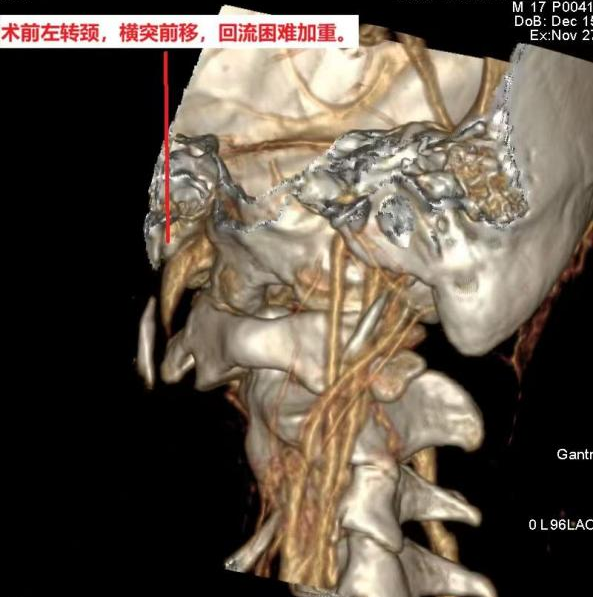

孙晓川教授团队多年来一直关注“脑鸣”及头颈部静脉系统疾病,并联合放射科李琦、陶黎团队进行了深入研究;接诊患者后,经术前详尽的影像学检查,发现其右侧颈内静脉被寰椎横突卡压,转头时血管竟完全闭塞,找到了引起患者大脑“神秘声响”的病根(图片由放射科刘传提供)。

手术区域毗邻颈椎、重要神经、颈部大血管,风险极高。为确保手术安全有效,神经外科(金山病区)脑血管亚专业组与脊柱脊髓亚专业组强强联合,为患者实施了精准手术。经过数小时鏖战,成功完成了西南地区首例寰椎横突部分磨除联合颈内静脉减压术!